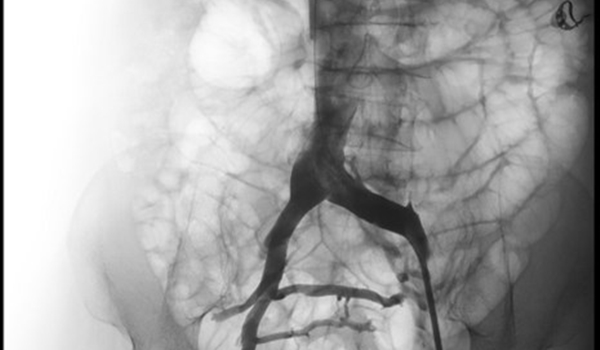

Tại đây, các bác sĩ khoa Lồng ngực mạch máu của BV đã chẩn đoán bệnh có nguồn gốc từ hội chứng chèn ép tĩnh mạch chậu và tắc mạch huyết chân, cần phải điều trị tải thông mạch máu. Sau đó bà G. được các bác sĩ tại bệnh viện nong bóng và đặt stent vào tĩnh mạch chậu, tải thông dòng máu về tim. Sau 2 điều trị, chân bà đã giảm phù được gần 50% so với trước khi can thiệp.

Tại đây, các bác sĩ khoa Lồng ngực mạch máu, BV ĐH Y Dược chẩn đoán bệnh nhân bị suy tĩnh mạch giai đoạn cuối do hội chứng chèn ép tĩnh mạch chậu. Sau quá trình thăm khám, các bác sĩ điều trị cho bà H theo phương pháp điều trị bằng nong bóng và đặt stent tải thông tĩnh mạch chậu thành công.

Theo bác sĩ Lê Thanh Phong, với kỹ thuật này bệnh nhân sẽ được nong bóng và đặt giá đỡ tĩnh mạch (stent) chỉ qua một vết đâm kim ở vùng bẹn đùi. Sau khi thực hiện thủ thuật này, người bệnh có thể đi lại vài giờ sau mổ và có thể xuất viện trong ngày.